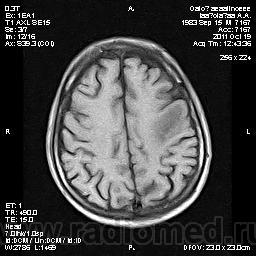

Молодой человек, жалуется только на головные боли и слабость в правой руке и ноге (около месяца).

Пациент полуасоциальный, нельзя исключить анамнез наркоманский....

ППН (включая ячейки пирамидок и сосцевидные отростки) тотально заполнены жидкостным компонентом...

Колеги, спасибо за высказывания. В данном случае про наркоманский анамнез указано не спроста... Есть мнение, что в этом лежит точка отсчета.... По поводу абсцесса и гематомы - не согласен; по поводу первого - нет соответствющей клиники, по поводу второго - не характерна локализация и сигнальные характеристики. Не буду томить общественность касательно собственного мнения. Есть две гипотезы, о которых думается в данном случае: прогрессирующая лейкоэнцефалопатия и новообразование... Но без контраста их не разрешить...